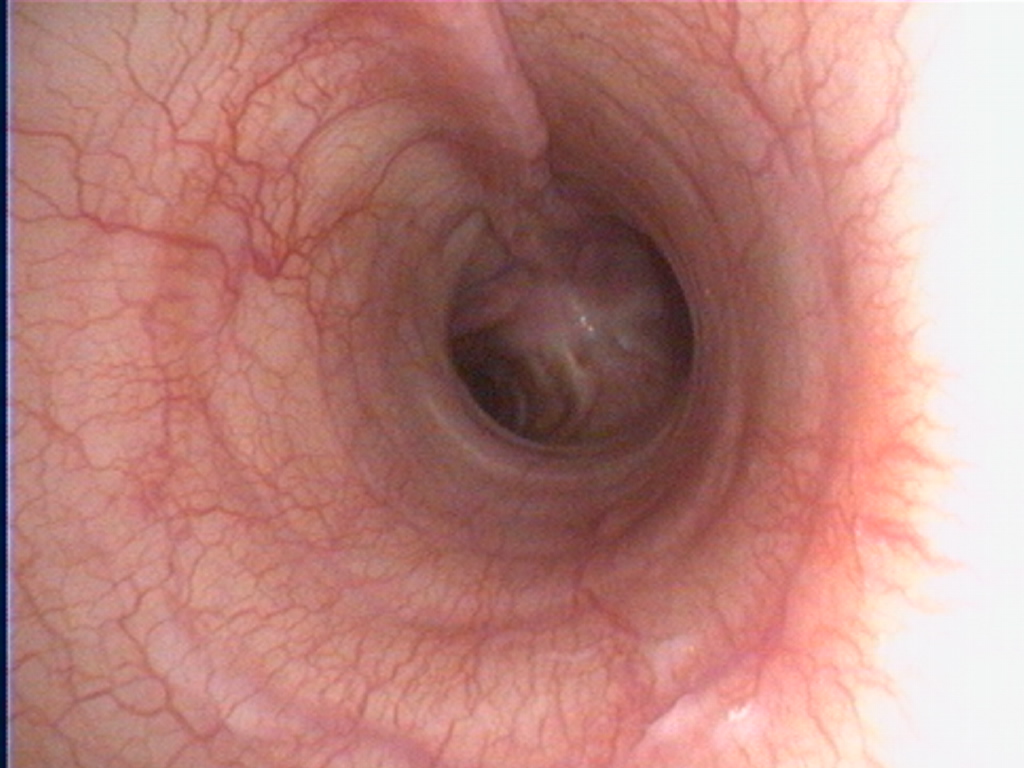

Endoscopie des voies respiratoires sur un chien.

De gauche à droite : larynx, trachée avec la carène, bronches.